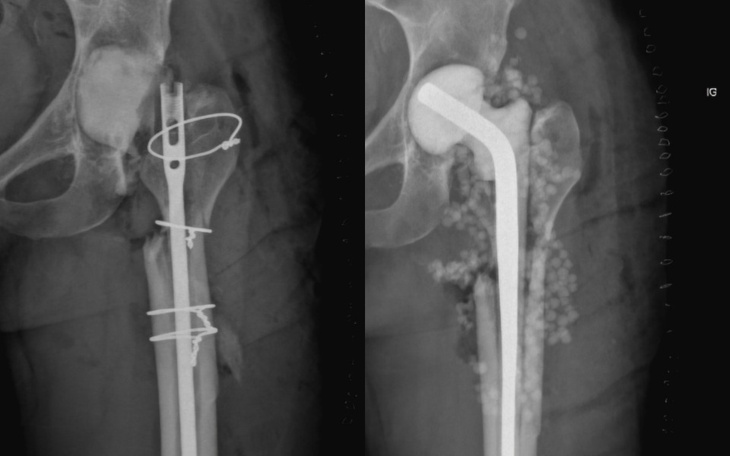

Kość, w miejscu najbardziej zniszczonym, zaczęła się w końcu zrastać 🤌